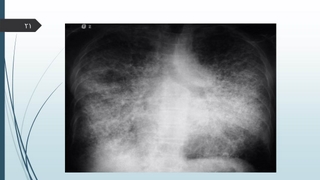

تشخيص :

Pulmonary Alveolar Microlithiasis